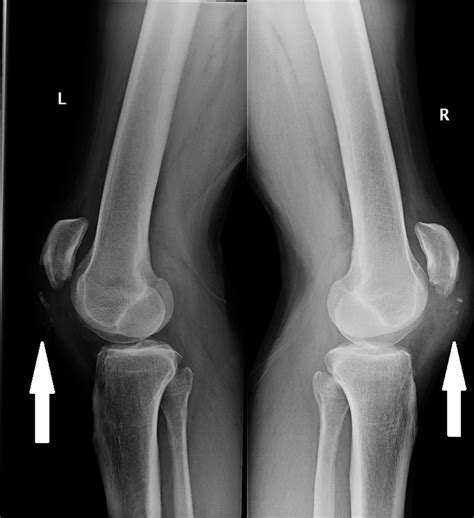

The primary symptom of a patellar tendon tear is a sudden, severe pain in the front of the knee, often accompanied by a popping or snapping sensation. Individuals may also experience swelling, bruising, and difficulty walking or bearing weight on the affected leg. A thorough physical examination, including a review of medical history and a series of tests to assess knee function and stability, is essential for diagnosis. Imaging studies, such as X-rays or magnetic resonance imaging (MRI), may be used to confirm the diagnosis and rule out other potential causes of knee pain. A study published in the Journal of Orthopaedic and Sports Physical Therapy found that MRI scans have a sensitivity of 95% and a specificity of 98% in diagnosing patellar tendon tears.